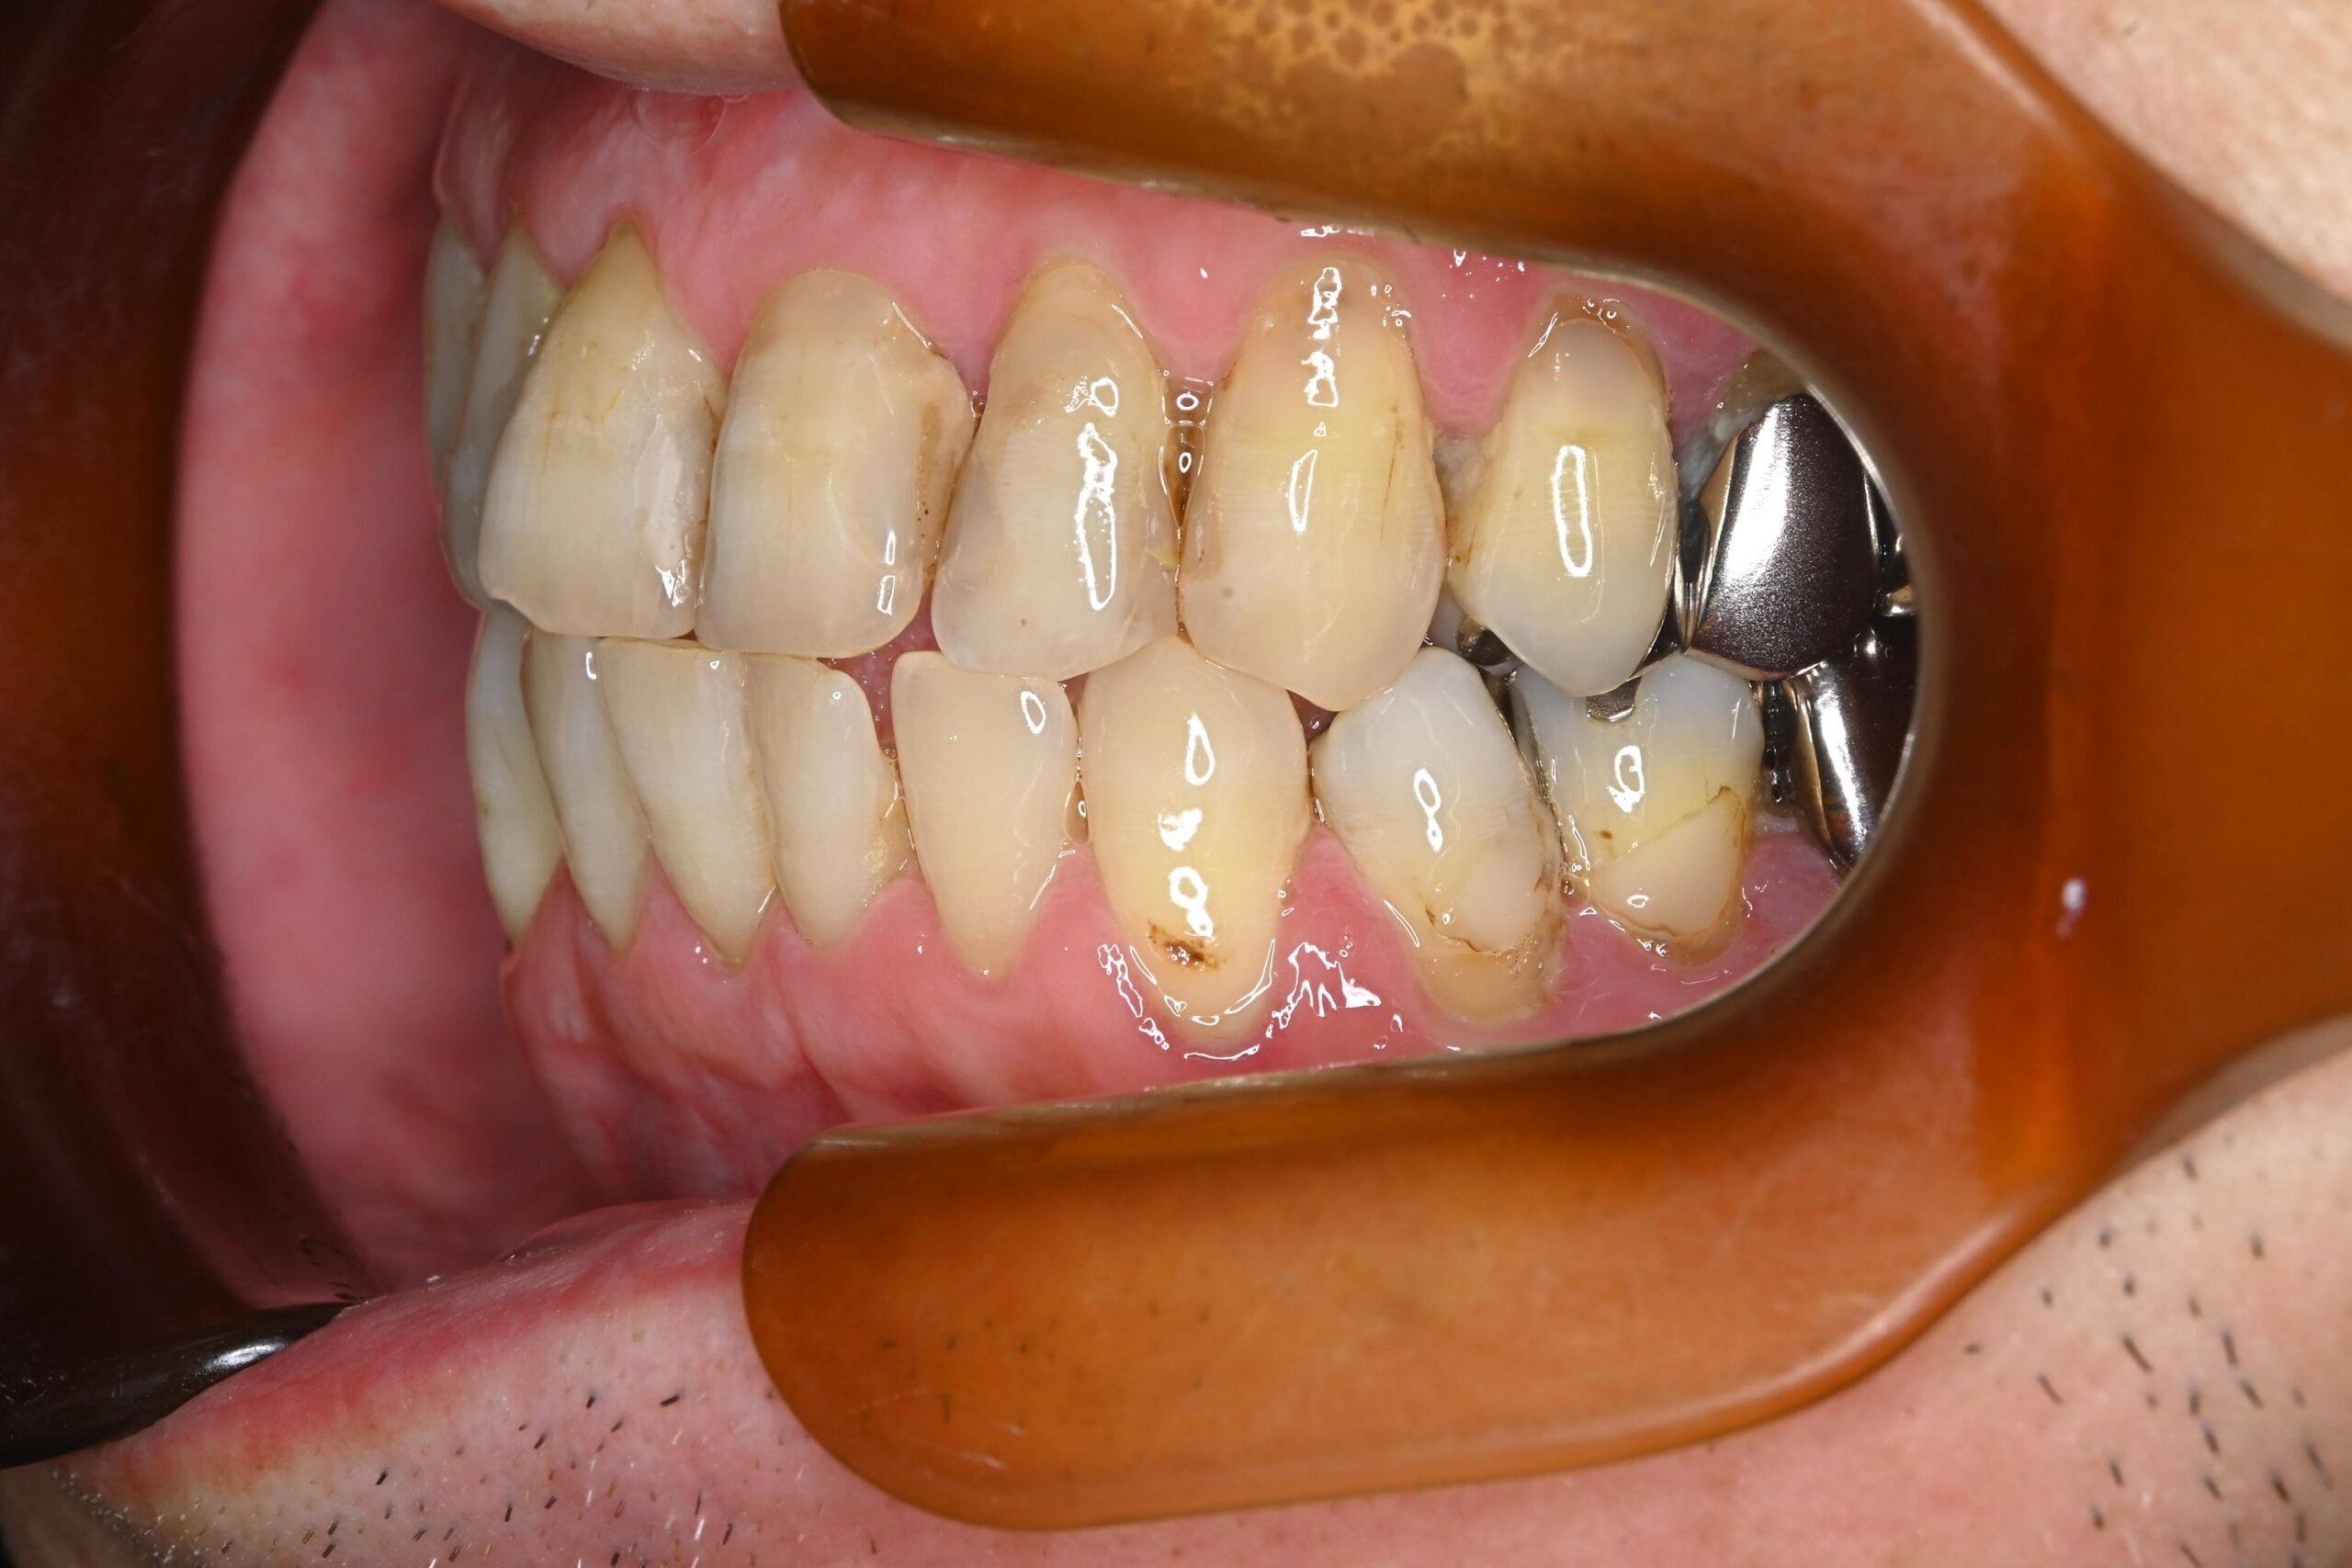

初診時の口腔内の状態:

お口全体に虫歯や歯周病の原因となるプラーク(歯垢)が多く付着していました。右上奥歯は重度の虫歯で歯冠部(歯の頭)が失われており、左下奥歯は過去の治療箇所から細菌が入り込み、根の先に炎症が起きている状態でした。

また、左右の奥歯にはWSD(楔状欠損)があり、知覚過敏も見られました。

単なる虫歯だけでなく、「切端咬合(せったんこうごう)」という噛み合わせの不調和が根本的な問題であると診断しました。この噛み合わせにより奥歯に過度な負担がかかり、知覚過敏や歯の損傷を引き起こしていました。

Before